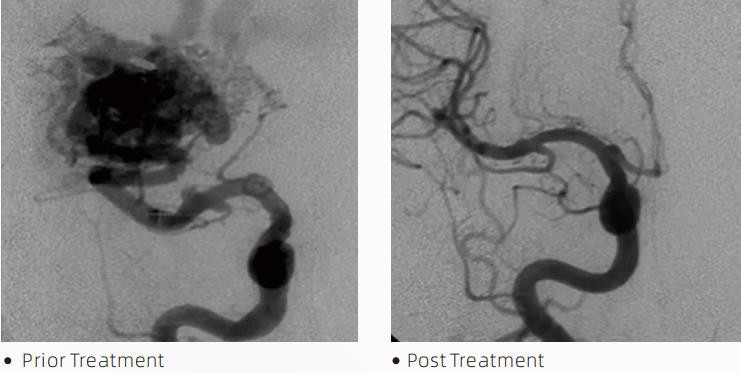

La LavaTMLiquid Embolic System és una teràpia endovascular intervencionista per al tractament de malformacions cerebrovasculars. La malformació cerebrovascular fa referència a un grup d'anomalies neurovasculars benignes o malignes que poden provocar hemorràgia intracranial, infart cerebral, isquèmia cerebral i altres malalties. El sistema d'embolització líquida és un dispositiu mèdic administrat mitjançant una simple inserció intravascular, que embolitza vasos sanguinis cerebrals anormals mitjançant la injecció d'un material fluid especial. El material fluid forma una embòlia de teixit controlada dins dels vasos sanguinis, que pot reduir l'impacte de les malformacions cerebrovasculars en els pacients. Per accedir al lloc d'embolització s'utilitza un micro catèter de lliurament compatible amb DMSO que està indicat per al seu ús en la neurovasculatura. L'agent embòlic líquid de lava és un sistema d'agent embòlic líquid no adhesiu format per un copolímer EVOH (alcohol etilè vinílic) dissolt en DMSO (sulfòxid de dimetil) i pols de tàntal micronitzat en suspensió per proporcionar contrast per a la visualització sota fluoroscòpia. LavaTMestà disponible en tres formulacions de producte, LAVA-12, LAVA-18 i LAVA-34. LAVA-12: recomanat per alimentar microvasos distals i a través de petits alimentadors. LAVA-18: recomanat quan s'alimentaran les injeccions pediculars es realitzaran prop del nidus; LAVA-34: recomanat per embolitzar un flux més alt i components fistulosos més grans.